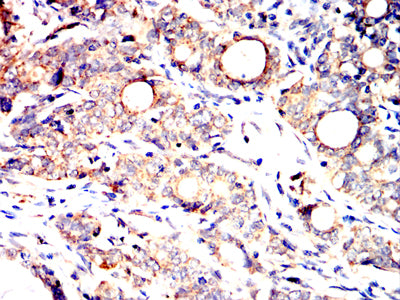

分类: 科研抗体货号: 32337别名: BYK; Dtk; RSE; Rek; Sky; Tif; Etk-2应用: IHC,FCM反应种属: Human

分类: 科研抗体货号: 32350别名: K14; NFJ; CK14; EBS1; EBS3; EBS4; EBS1A; EBS1B; EBS1C; EBS1D应用: WB,IHC,IF,FCM反应种属: Human

分类: 科研抗体货号: 32340别名: A4; STV1; VPH1; VPP2; DRTA3; RTA1C; RTADR; ATP6N2; RDRTA2; ATP6N1B应用: IHC,FCM反应种属: Human

分类: 科研抗体货号: 32349别名: CL2; DCK2; CLIK2; DCDC3; CLICK2; DCDC3B; DCAMKL2; CLICK-II应用: IHC,FCM反应种属: Human

分类: 科研抗体货号: 32334别名: GLUT14; SLC2A3P3应用: IHC,IF反应种属: Human

分类: 科研抗体货号: 32339别名: AOM; ANFH; SEDC; STL1; COL11A3应用: IHC,FCM反应种属: Human

分类: 科研抗体货号: 32333别名: TLT2; TLT-2; C6orf76; dJ238O23.1应用: IHC,IF,FCM反应种属: Human